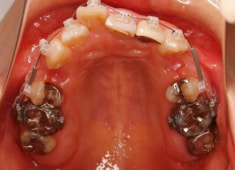

治療開始時